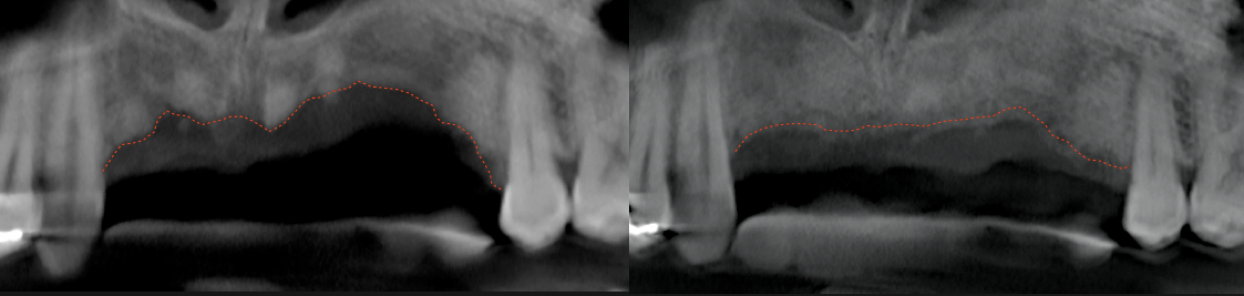

S.M.A.R.T. VERTICAL & HORIZONTAL AUGMENTATION

Performed in a single office procedure using local anesthesia and two small incisions. No flaps, no tenting screws and no membranes were utilized. Sufficient horizontal and vertical bone volume was achieved to allow future placement of multiple implants.

bone-graft-smart

Substantial vertical augmentation in the area of the failed anterior implants accomplished with the S.M.A.R.T. method.  The patient reported minimal pain and moderate swelling. Periosteal elevation was difficult due to extensive scar tissue.